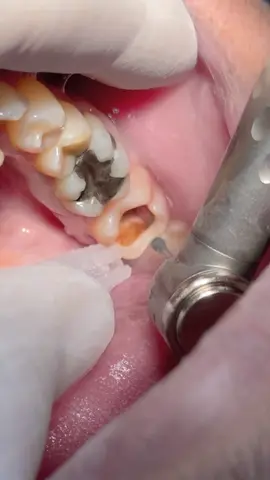

Deep tooth caries with root canal treatment #dentist #dental #dentistry